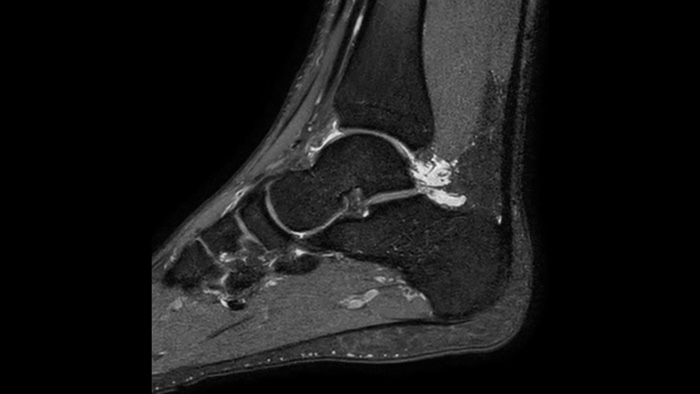

Affidabilità diagnostica Risoluzione spaziale fino al 60% più elevata, con lo stesso tempo di scansione.4

1 Anche nella remota eventualità che venga meno la tenuta ermetica del magnete, la fuoriuscita di una quantità trascurabile di elio non influirebbe in modo sostanziale sul livello di ossigeno presente nella sala. 2 Rispetto alle scansioni Philips senza Compressed SENSE. 3 Per una frequenza cardiaca bassa (50 bpm), rispetto alle scansioni Philips senza Compressed SENSE. 4 In scansioni 3D MSK VIEW isotropiche, rispetto alle scansioni Philips senza Compressed SENSE.